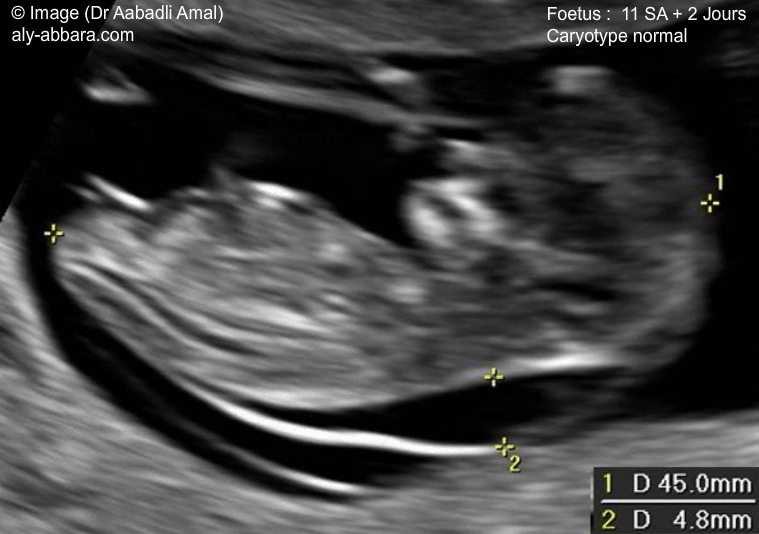

L'échographie de la clarté nucale est un test de dépistage qui permet d'évaluer le risque que votre bébé soit atteint du syndrome de Down (trisomie 21) BabyCenter Canada BabyCenter Canad ;468 Down syndrome) », Prenat Diagn, vol 30, no 1, 10, p 5764 (PMIDSpé chir et gynécoobst, s21DP 34,02 EUR Spé chir et gynécoobst, s21DP OPTAM 37,05 EUR Spé chir et gynécoobst, non conventionné 34,02 EUR Il s'agit de la choriocentèse, qui consiste à prélever un très petit fragment du placenta (villosités) Ce geste est réalisé entre 10 et 12 semaines d' aménorrhée , en cas de fort

Clarté nucale prix La clarté nucale est donc tjrs mesurée entre 35 et 39mmTout le reste est tjrs tout à fait normal Je n aurai pas de biopsie car je suis sous aspegic et qu avec mes antécédent de fc, le ratio beneficerique est pour eux important Ventriculomégalie et kystes plexus choroïdes J'ai fait l'échographie morphologique vendredi matin dernier et il en est ressorti que les ventricules cérébraux de mon papoute sont plus gros que la moyenne (moyenne ne devrait pas dépasser 10mm et moi j'en suis à 10,5mm) De plus, ils ont décelé des kystes sur les plexus choroïdesLe fœtus continue doucement sa grossesse et atteint en cette vingtetunième semaine de grossesse, la taille de 24 cm pour environ 450 grammes Faisons le point sur cette 19ème semaine d'aménorrhée 19ème semaine de grossesse pour la maman 19 SG/21SA, le ventre commence